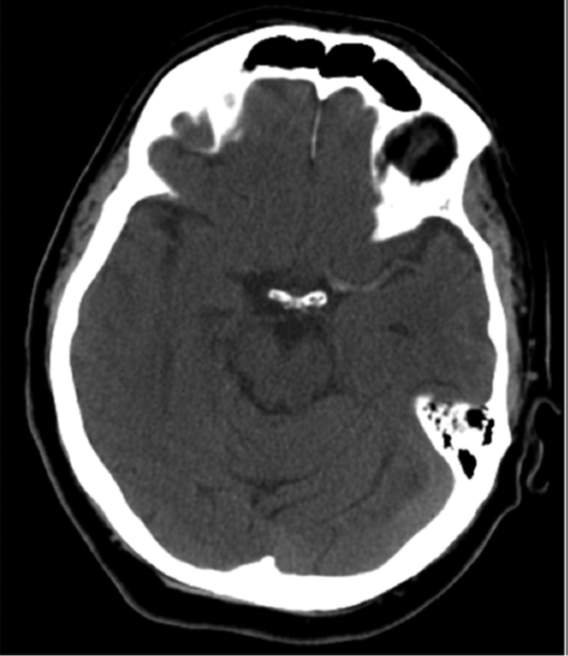

Dịch tễ học U não tiên phát ác tính vẫn là một thách thức trong y khoa. U nguyên bào thần kinh đệm (còn gọi là u tế bào thần kinh đệm độ IV, u sao bào độ IV) là u não tiên phát phổ biến và ác tính nhất. U nguyên bào thần kinh đệm là hình ảnh thu nhỏ của một nhóm u tế bào thần kinh đệm […]